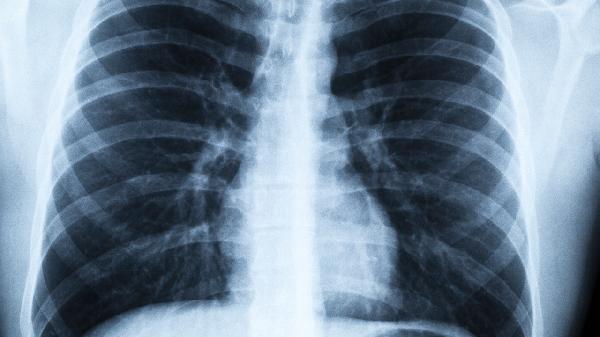

50岁后身体出现这些信号别大意!医生提醒:肺癌早期症状常被忽视

建议每年做一次低剂量螺旋CT检查,这是目前筛查早期病变最有效的手段。长期吸烟者、有家族史的人群,可以将筛查年龄提前到45岁。